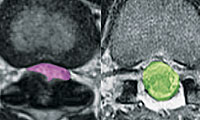

허리를 돌리는 동작에서 부상이 없도록 하려면 스트레칭을 잘해야 합니다. 허리 통증으로 골프를 쉬었다가 복귀할 때 어떤 코어 근력이 부족한지 파악하고 해당 운동을 열심히 해야 합니다. 코어 근육이 받쳐줘야 좋은 플레이를 통증 없이 할 수 있습니다. 플랭크, 크런치, 버드도그(bird dog) 운동을 하면 좋습니다. 코어 근육을 강화하기 위해 아령·케틀벨을 들고 스쿼트를 하기도 합니다. 허리 회전 유연성과 코어 근육을 발달시킬 수 있는 운동 두 가지를 배워 봅시다.